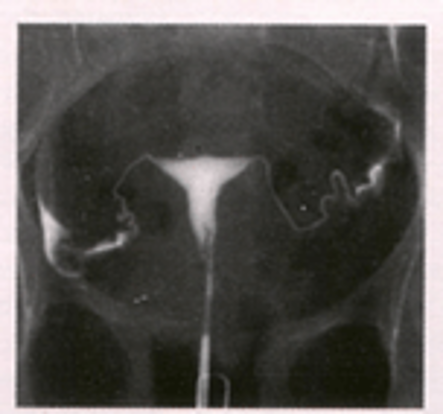

How to check fallopian tube patency?